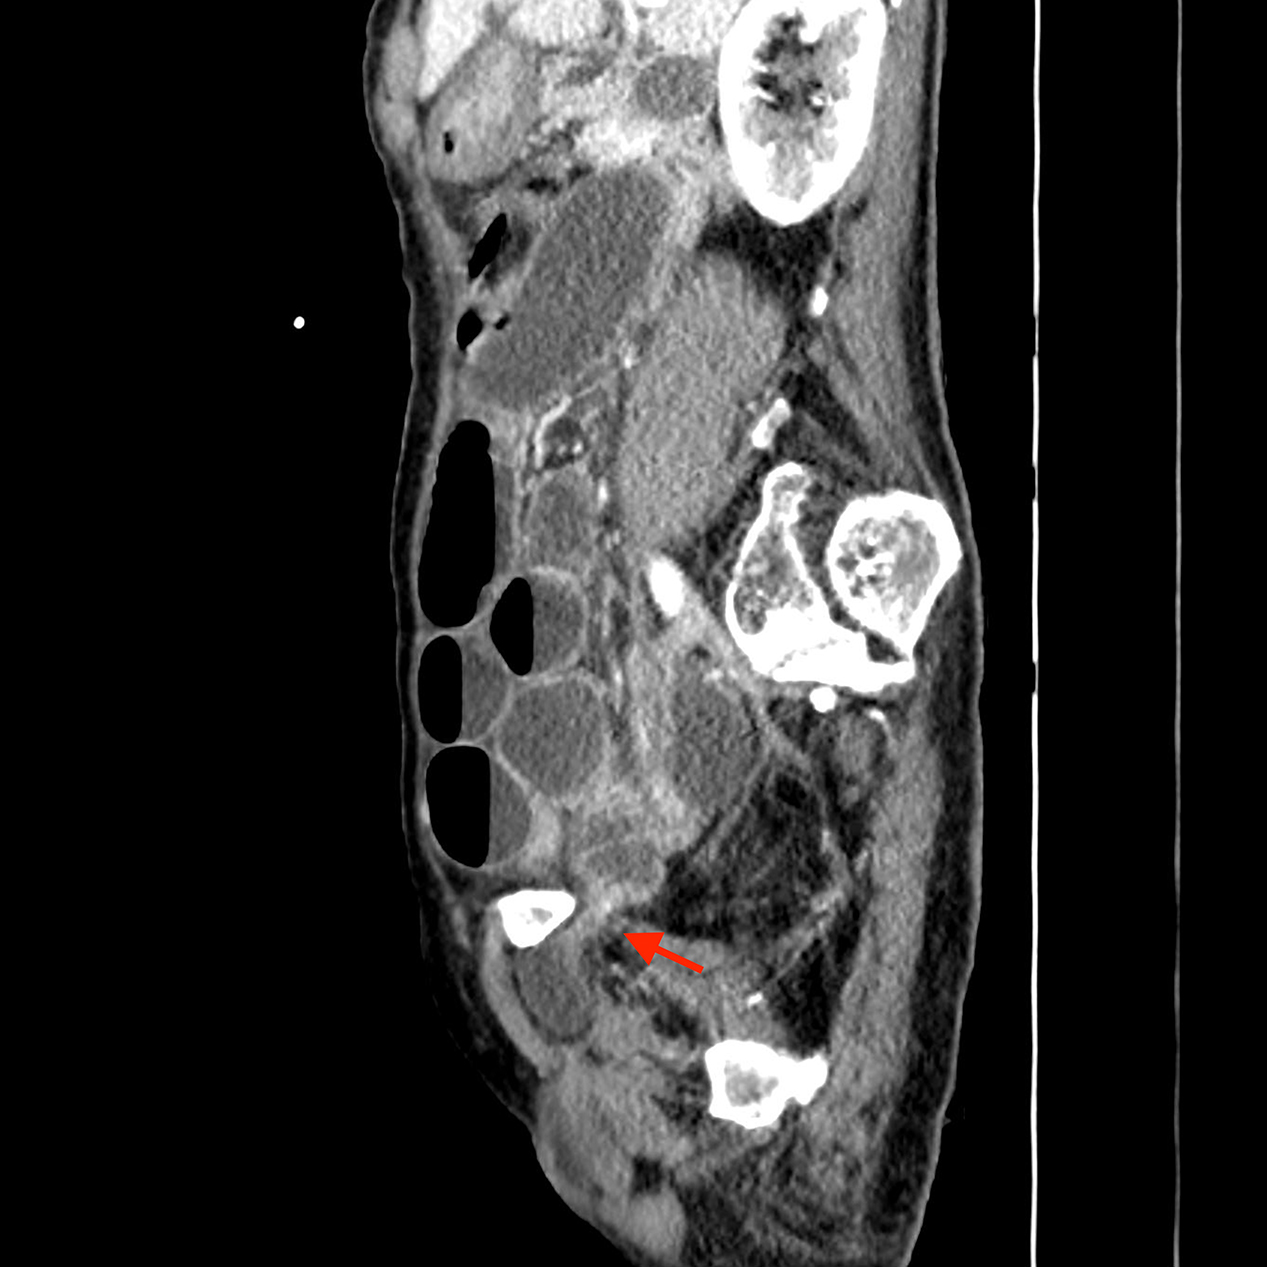

Figure 3

Sagittal image demonstrating entrapped obturator hernia and small bowel obstruction.